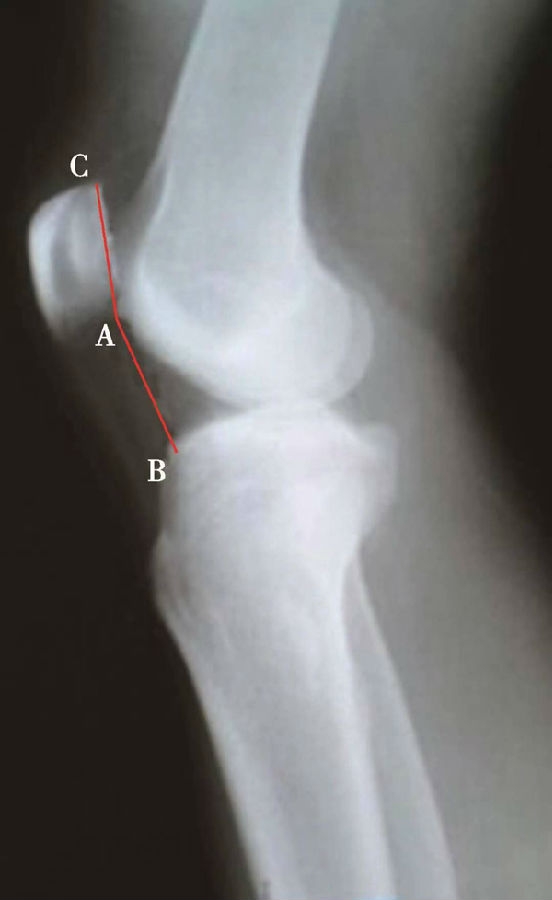

如图示:AB为髌骨关节面最低点到胫骨平台轮廓前上角最短的距离,AC是髌骨关节面的长度。Caton指数=AB/AC(图1)。

图1

图2 Caton指数=AB/AC=1.10,为正常髌骨高度

临床工作中常常使用其来估计胫骨结节移位的效果。正常人的Caton指数=1,正常范围0.8~1.2(图2)。需要注意的是:术前规划胫骨结节需要移位的理论距离为AB-AC,这就是需要将胫骨结节向远端移位的最大距离。但在术中胫骨结节转移的距离往往要小于这个距离,避免因过度移位造成医源性的低位髌骨。